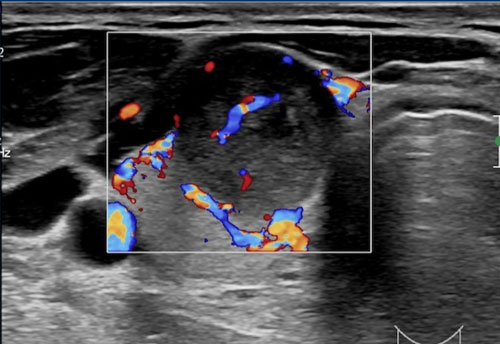

Echogenicity

Trường hợp 1

Đầu tiên, hãy quan sát hình ảnh siêu âm.

Tiến hành phân tích bên dưới.

Có hiện tượng tăng âm phía sau, gợi ý rằng tổn thương này có thể có bản chất dạng nang.

Trong những trường hợp như vậy, siêu âm Doppler màu có thể hữu ích để đánh giá thêm; tuy nhiên, kỹ thuật này không được thực hiện trong trường hợp này.